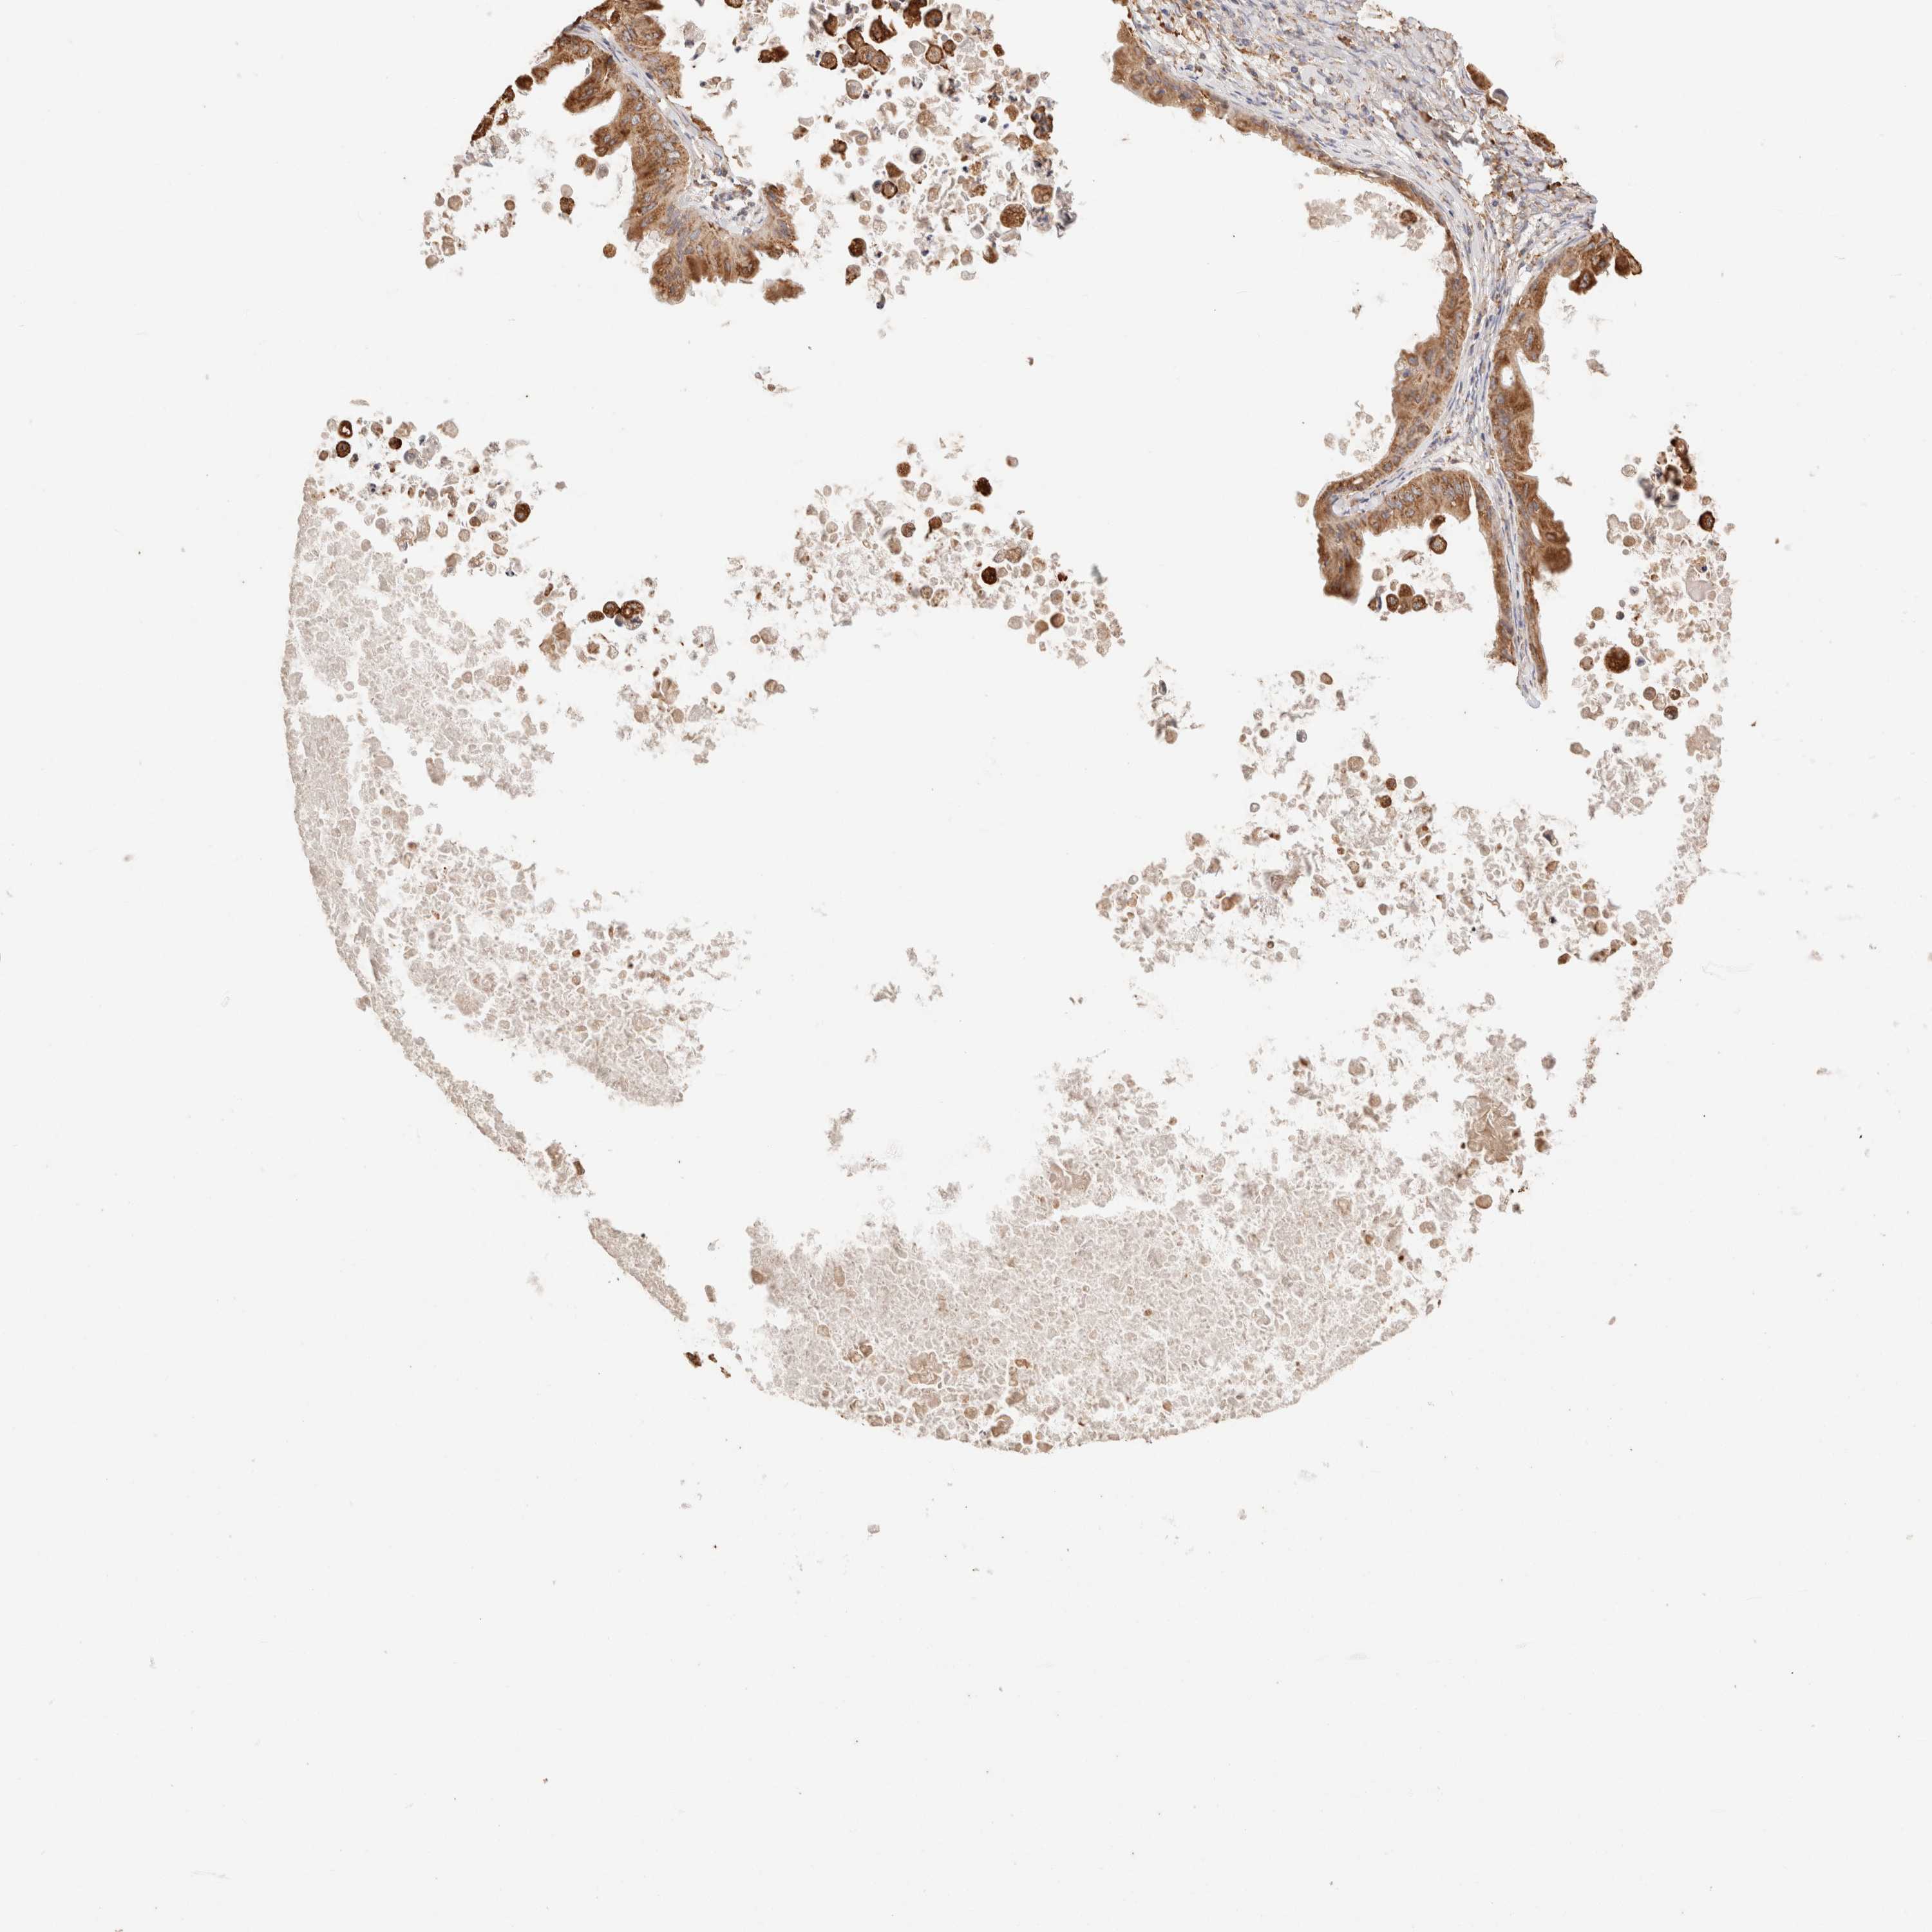

OVARIAN CANCER - Protein expressioni

A mouse-over function shows sample information and annotation data. Click on an image to view it in a full screen mode. Samples can be filtered based on level of antibody staining by selecting one or several of the following categories: high, medium, low and not detected. The assay and annotation is described here.

Note that samples used for immunohistochemistry by the Human Protein Atlas do not correspond to samples in the TCGA dataset.

Antibody stainingi

Antibody staining in the annotated cell types in the current human tissue is reported as not detected, low, medium, or high, based on conventional immunohistochemistry profiling in selected tissues. This score is based on the combination of the staining intensity and fraction of stained cells.

Each image is clickable and will lead to virtual microscopy that enables deeper exploration of all samples and also displays staining intensity scores, fraction scores and subcellular localization as well as patient and tissue information for each sample.

Antibody HPA007641

Antibody CAB022464

Cystadenocarcinoma, serous, NOS

Carcinoma, endometroid

Cystadenocarcinoma, mucinous, NOS

Carcinoma, NOS